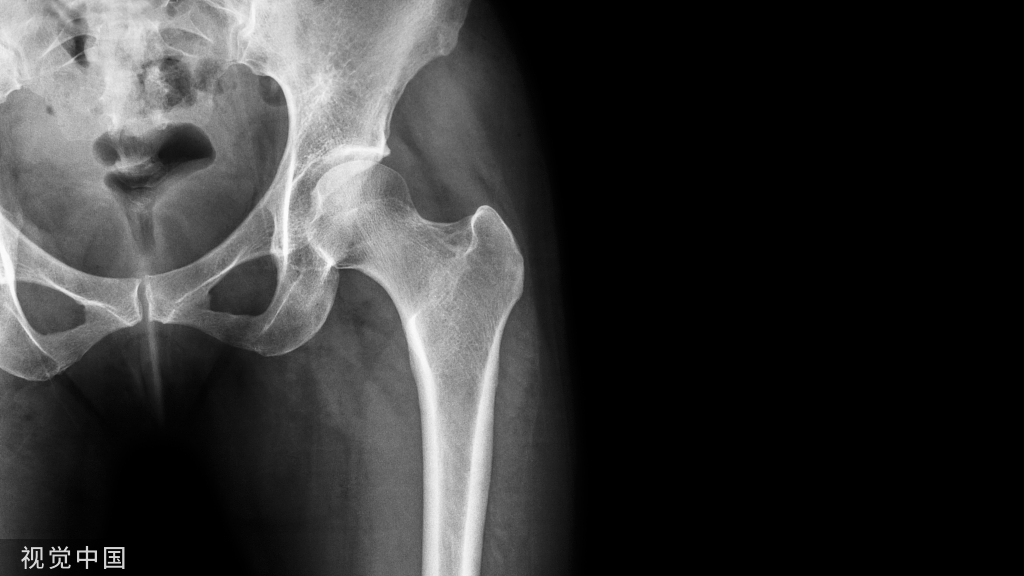

膝关节单髁置换手术是膝关节骨关节炎阶梯治疗的重要部分。是针对膝关节单间室的病变,以尽可能多地保留患者膝关节的正常结构为目的的手术。与传统的全膝关节置换手术相比,单髁置换手术操作更加微创化,术后步态更加自然、功能恢复速度更快、满意度更高;并且后期翻修相对容易。因此以牛津单髁(Oxford)为代表的单髁置换手术在临床上得到广泛应用。下面以牛津单髁置换手术视频为基础,图文结合,以分享如何规范进行牛津单髁置换手术的方法。